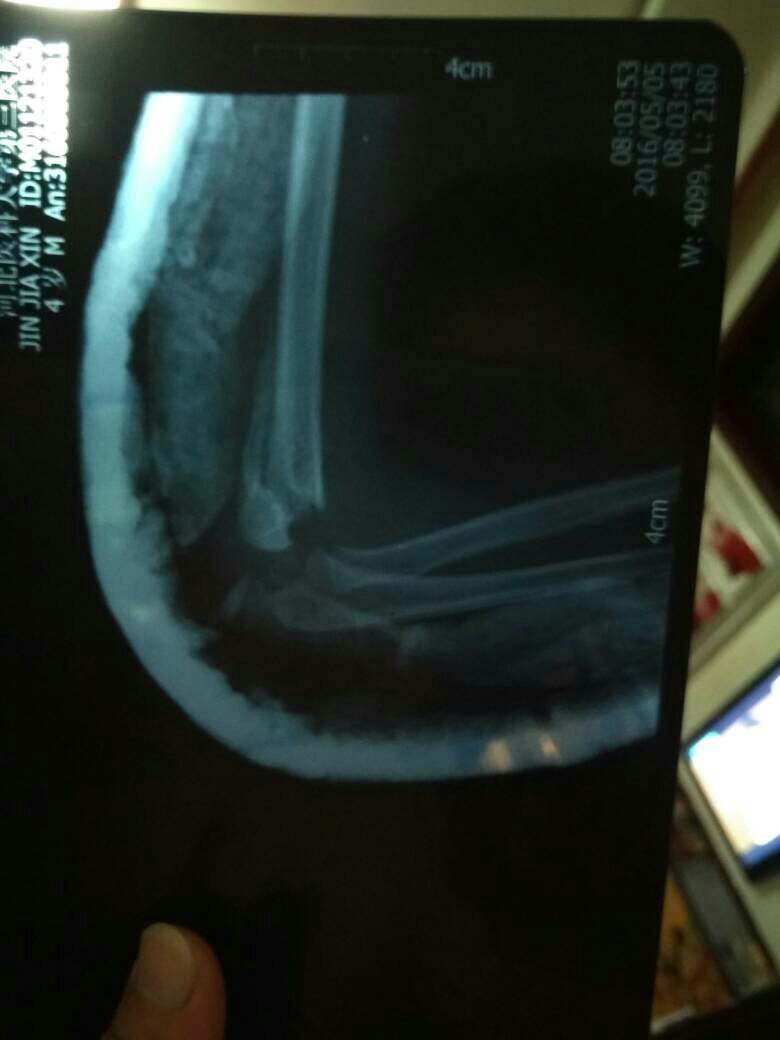

3周宝宝髁上骨折,没做手术 现在3星期,拆石膏了 胳膊伸不直 点击展开 匿名用户 2016-05-05 23:23 满意回答 最近复查过片子吗?胳膊那有肿胀吗?摸他疼吗 cn#GBBkLappV 2016-05-06 06:01 宝宝知道提示您:回答为网友贡献,仅供参考。 相关问题 手腕骨折一个月了拆了石膏以后怎么一个胳膊都没有力气… 两岁多小孩夏天胳膊骨折打石膏会不会长疮?皮肤会不会捂坏 宝宝胳膊骨折打了石膏晚上睡觉睡不安稳不停地哭怎么办